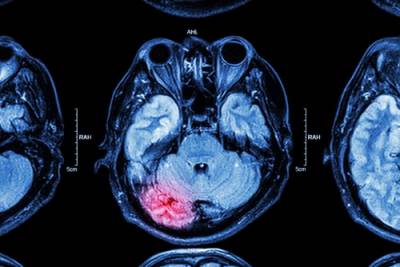

The treatment for brain injuries might be different depending on the type of damage to the brain. For example, the way a concussion is treated is different than a skull fracture. The first step in treating a brain injury involves imaging tests. A computerized tomography (CT) scan uses X-rays for a comprehensive view of the brain and is typically performed when a victim comes to the emergency room. A CT scan can reveal fractures as well as hemorrhages, hematomas, contusions, or swelling. Magnetic resonance imaging (MRI) uses magnets and radio waves for a detailed view of the brain. This test may be conducted once a patient’s condition stabilizes.